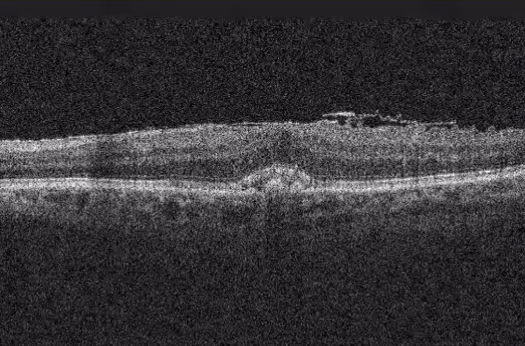

Este guia explica tudo o que você precisa saber sobre a cirurgia de membrana epirretiniana (MER): quando ela é indicada, como decidir se é o caminho certo para você, o que acontece durante o procedimento e como é a recuperação. Também abordamos taxas de sucesso, possíveis riscos e sinais de alerta no pós-operatório, para que você tenha informações práticas e claras para tomar uma decisão informada sobre a sua saúde visual.